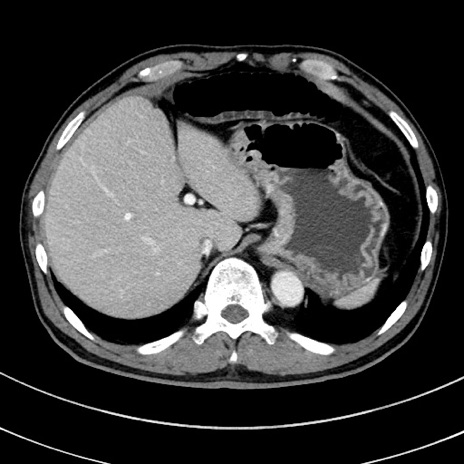

症例8(横断像)

【症例】 60歳代男性

【主訴】 黒色吐物

【現病歴】 4日前から嘔気自覚、2日前の朝食後にも嘔気あり、自分で手で嘔吐反射起こし嘔吐したところ血が混ざっていたため受診。

【既往歴】 5年前汎発性腹膜炎を伴う急性虫垂炎で手術、高血圧、前立腺肥大症、高脂血症

【身体所見】 腹部正中に手術癩痕あり 腹部平坦・軟圧痛なし膨満感あり

【データ】WBC 8400、CRP 4.54